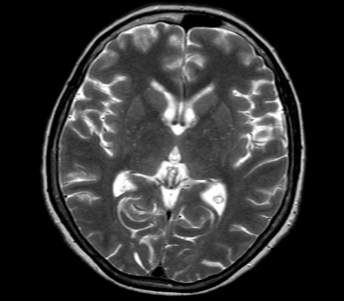

Ovdje je prikazan kranijum u transverzalnoj ravni u T1 i T2 vremenu. Uočljiva je razlika koja ukazuje na to da je u T1 vremenu bijela masa svjetlija, u odnosu na sivu masu i cerebrospinalnu tečnost, dok su u T2 vremenu ove strukture predstavljene kao negativ T1 vremena.